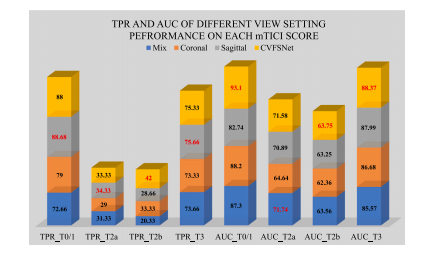

Fig. 5. TPR and AUC of 𝑀𝑖𝑥, 𝐶𝑜𝑟𝑜𝑛𝑎𝑙, 𝑆𝑎𝑔𝑖𝑡𝑡𝑎𝑙 and CVFSNet on each mTICI score ofAmTICIS, best results are indicated in red.

图5:在自动改良脑梗死溶栓分级评分(AmTICIS)数据集的每个mTICI评分等级上,“混合(Mix)”、“冠状位(Coronal)”、“矢状位(Sagittal)”以及跨视图融合评分网络(CVFSNet)的真阳性率(TPR)和曲线下面积(AUC),最优结果以红色标出。

We proposed a CVFSNet based on dual-view angiographic imagesfor automatic, objective, end-to-end mTICI scoring and built a crossview fusion module, CVFM, to integrate, aggregate, and complementfeatures from different views. In the ablation experiments, we firstcompared the performance between single-view and dual-view inputs,demonstrating the necessity of dual-view image input. This may bedue to the fact that DSA imaging is projection-compressed and intracranial vessel structures are complex, leading to vessel overlap insingle-view images, which affects the model’s ability to characterizeblood flow accurately. Then, by comparing different methods of dualview feature fusion, we verified the effectiveness of the CVFM module.CVFM leverages prior positional knowledge of coronal and sagittalviews, constructs oblique sagittal features using trigonometric functionsand the Pythagorean theorem, and employs a transformer-like moduleto explore complementary relationships between coronal and sagittalfeatures, thereby building global dependencies and generating more expressive fused features, ultimately enhancing performance. In the comparative experiments, we compared our approach with some classicaland state-of-the-art video feature classification models, demonstratingsuperior performance andgood stability.In the dichotomized experiments, CVFSNet demonstrated performance exceeding 90% across all indicators, implying that CVFSNet mayhave the potential for clinical application in determining the adequacyof mTICI scores. However, our study also has limitations. Firstly, thesevideo feature classification methods that were compared in the comparative experiments only supported single-view inputs, which maydisadvantage their comparison in terms of performance. Additionally,the AmTICIS dataset constructed in this study only includes data forM1 segment stenosis, limiting its clinical applicability. In the future,we plan to expand the dataset to include more mTICI scoring datawith various vessel stenosis, such as Internal Carotid Artery (ICA), BaseArtery (BA), Anterior Cerebral Artery (ACA), and Posterior CerebralArtery (PCA) etc., thereby constructing a more comprehensive scoringdataset. Also, the sample size of AmTICIS can be further expanded byincorporating data from multiple centers to enhance its diversity.In conclusion, we propose a novel CVFSNet in this paper for automatic, objective, and end-to-end mTICI scoring. Specifically, CVFSNetemploys dual branches to simultaneously extract spatial–temporal features from coronal view and sagittal view, and these cross-view featuresare fused through a novel cross view fusion module that explores thepositional characteristics of coronal and sagittal views to fuse andgenerate a pseudo-oblique sagittal feature and deploys a transformerlike architecture to explore the correlation between different viewfeatures, ultimately constructing more representative features to enhance the scoring performance of the model. In addition, we providea newly collected and the first publicly available digital subtractionangiography image dataset with expert annotations (AmTICIS) for automatic mTICI scoring, which can effectively promote researchers toconduct studies of ischemic stroke based on DSA images and finallyhelp patients get better medical treatment. Extensive experimentationresults demonstrate the promising performance of our methods and theeffectiveness of the cross-view fusion module.

我们基于双视角血管造影图像提出了CVFSNet网络,用于实现自动、客观、端到端的脑梗死溶栓治疗改良分级(mTICI)评分,并构建了一个跨视角融合模块(CVFM),以整合、聚合和补充来自不同视角的特征。在消融实验中,我们首先比较了单视角输入和双视角输入的性能,结果表明了双视角图像输入的必要性。这可能是因为数字减影血管造影(DSA)成像是投影压缩的,且颅内血管结构复杂,导致单视角图像中出现血管重叠,从而影响了模型准确表征血流的能力。然后,通过比较不同的双视角特征融合方法,我们验证了CVFM模块的有效性。CVFM利用冠状面和矢状面的先验位置知识,使用三角函数和勾股定理构建斜矢状面特征,并采用类似Transformer的模块来探索冠状面和矢状面特征之间的互补关系,从而建立全局依赖关系,并生成更具表现力的融合特征,最终提升性能。在对比实验中,我们将我们的方法与一些经典的以及最先进的视频特征分类模型进行了比较,结果显示出我们的方法具有优越的性能和良好的稳定性。 在二分类实验中,CVFSNet在所有指标上的表现均超过了90%,这意味着CVFSNet在确定mTICI评分是否足够方面可能具有临床应用潜力。然而,我们的研究也存在局限性。首先,在对比实验中所比较的这些视频特征分类方法仅支持单视角输入,这在性能比较方面可能对它们不利。此外,本研究构建的AmTICIS数据集仅包含大脑中动脉M1段狭窄的数据,限制了其临床适用性。未来,我们计划扩展该数据集,纳入更多具有各种血管狭窄情况的mTICI评分数据,例如颈内动脉(ICA)、基底动脉(BA)、大脑前动脉(ACA)和大脑后动脉(PCA)等,从而构建一个更全面的评分数据集。同时,通过纳入多个中心的数据来进一步扩大AmTICIS的样本量,以提高其多样性。 总之,本文提出了一种新颖的CVFSNet网络,用于自动、客观、端到端的mTICI评分。具体而言,CVFSNet采用双分支同时从冠状面和矢状面提取时空特征,并且这些跨视角特征通过一个新颖的跨视角融合模块进行融合。该模块探索冠状面和矢状面的位置特征,以融合并生成伪斜矢状面特征,并部署了类似Transformer的架构来探索不同视角特征之间的相关性,最终构建出更具代表性的特征,以提升模型的评分性能。此外,我们提供了一个新收集的、首个带有专家注释的公开可用的数字减影血管造影图像数据集(AmTICIS),用于自动mTICI评分,这可以有效地推动研究人员基于DSA图像开展缺血性中风的研究,并最终帮助患者获得更好的治疗。大量的实验结果证明了我们方法的良好性能以及跨视角融合模块的有效性。

Table 1Performance comparison of deploying dual-view inputs and single-view inputs on AmTICIS. The best results are indicated in bold

表1:在自动改良脑梗死溶栓分级评分(AmTICIS)数据集上,使用双视图输入和单视图输入的性能比较。最优结果以粗体显示。